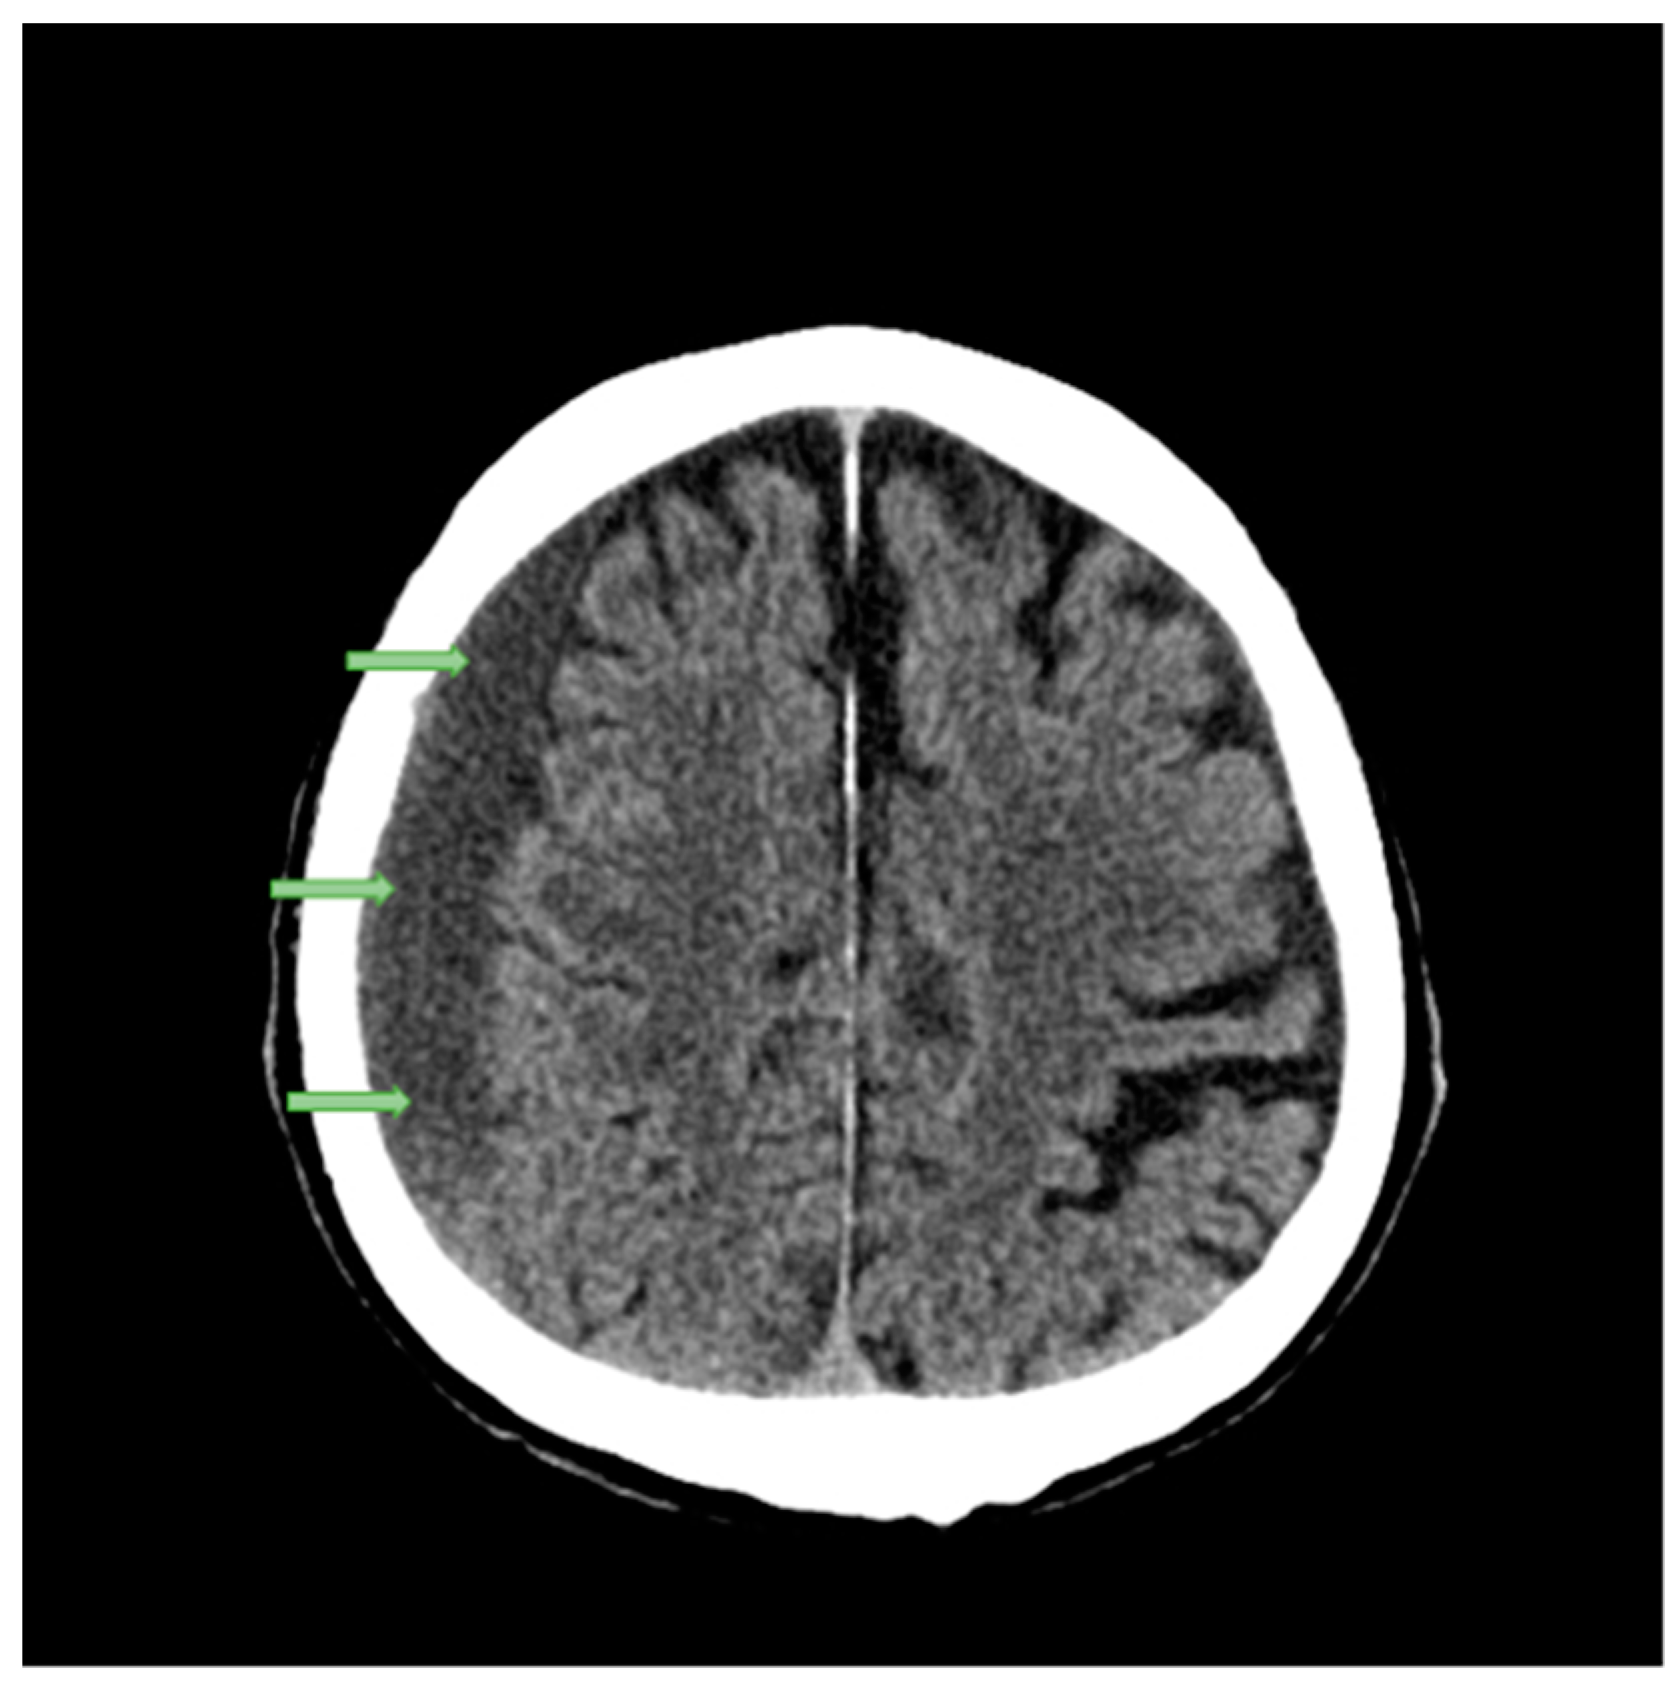

2.1. Case Studies